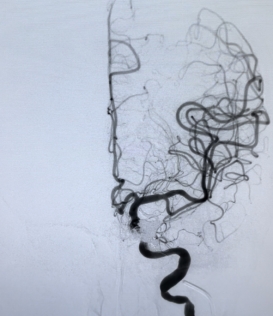

全科讨论手术方案后,一致认为要栓塞瘘口并保护好左侧颈内动脉的通畅,遂决定采用静脉途径使用“钢筋混泥土”(同时使用弹簧圈和液体栓塞剂)结构牢牢堵住瘘口。

3月16日13点,张卫东带领团队为患者行颈内动脉海绵窦瘘栓塞术,同时行股动脉、股静脉穿刺,微导管翻山越岭后进入海绵窦。为确保左侧颈动脉不受干扰,于颈动脉内置入球囊予以保护。

在团队的协作下,经过2个多小时惊心动魄的战斗,堵塞瘘口的“钢筋混泥土墙”终于修好啦。

术后患者停用麻药后逐渐清醒,清醒后耳鸣立即消失,结膜水肿缓解。

(栓塞术后,血管通畅)